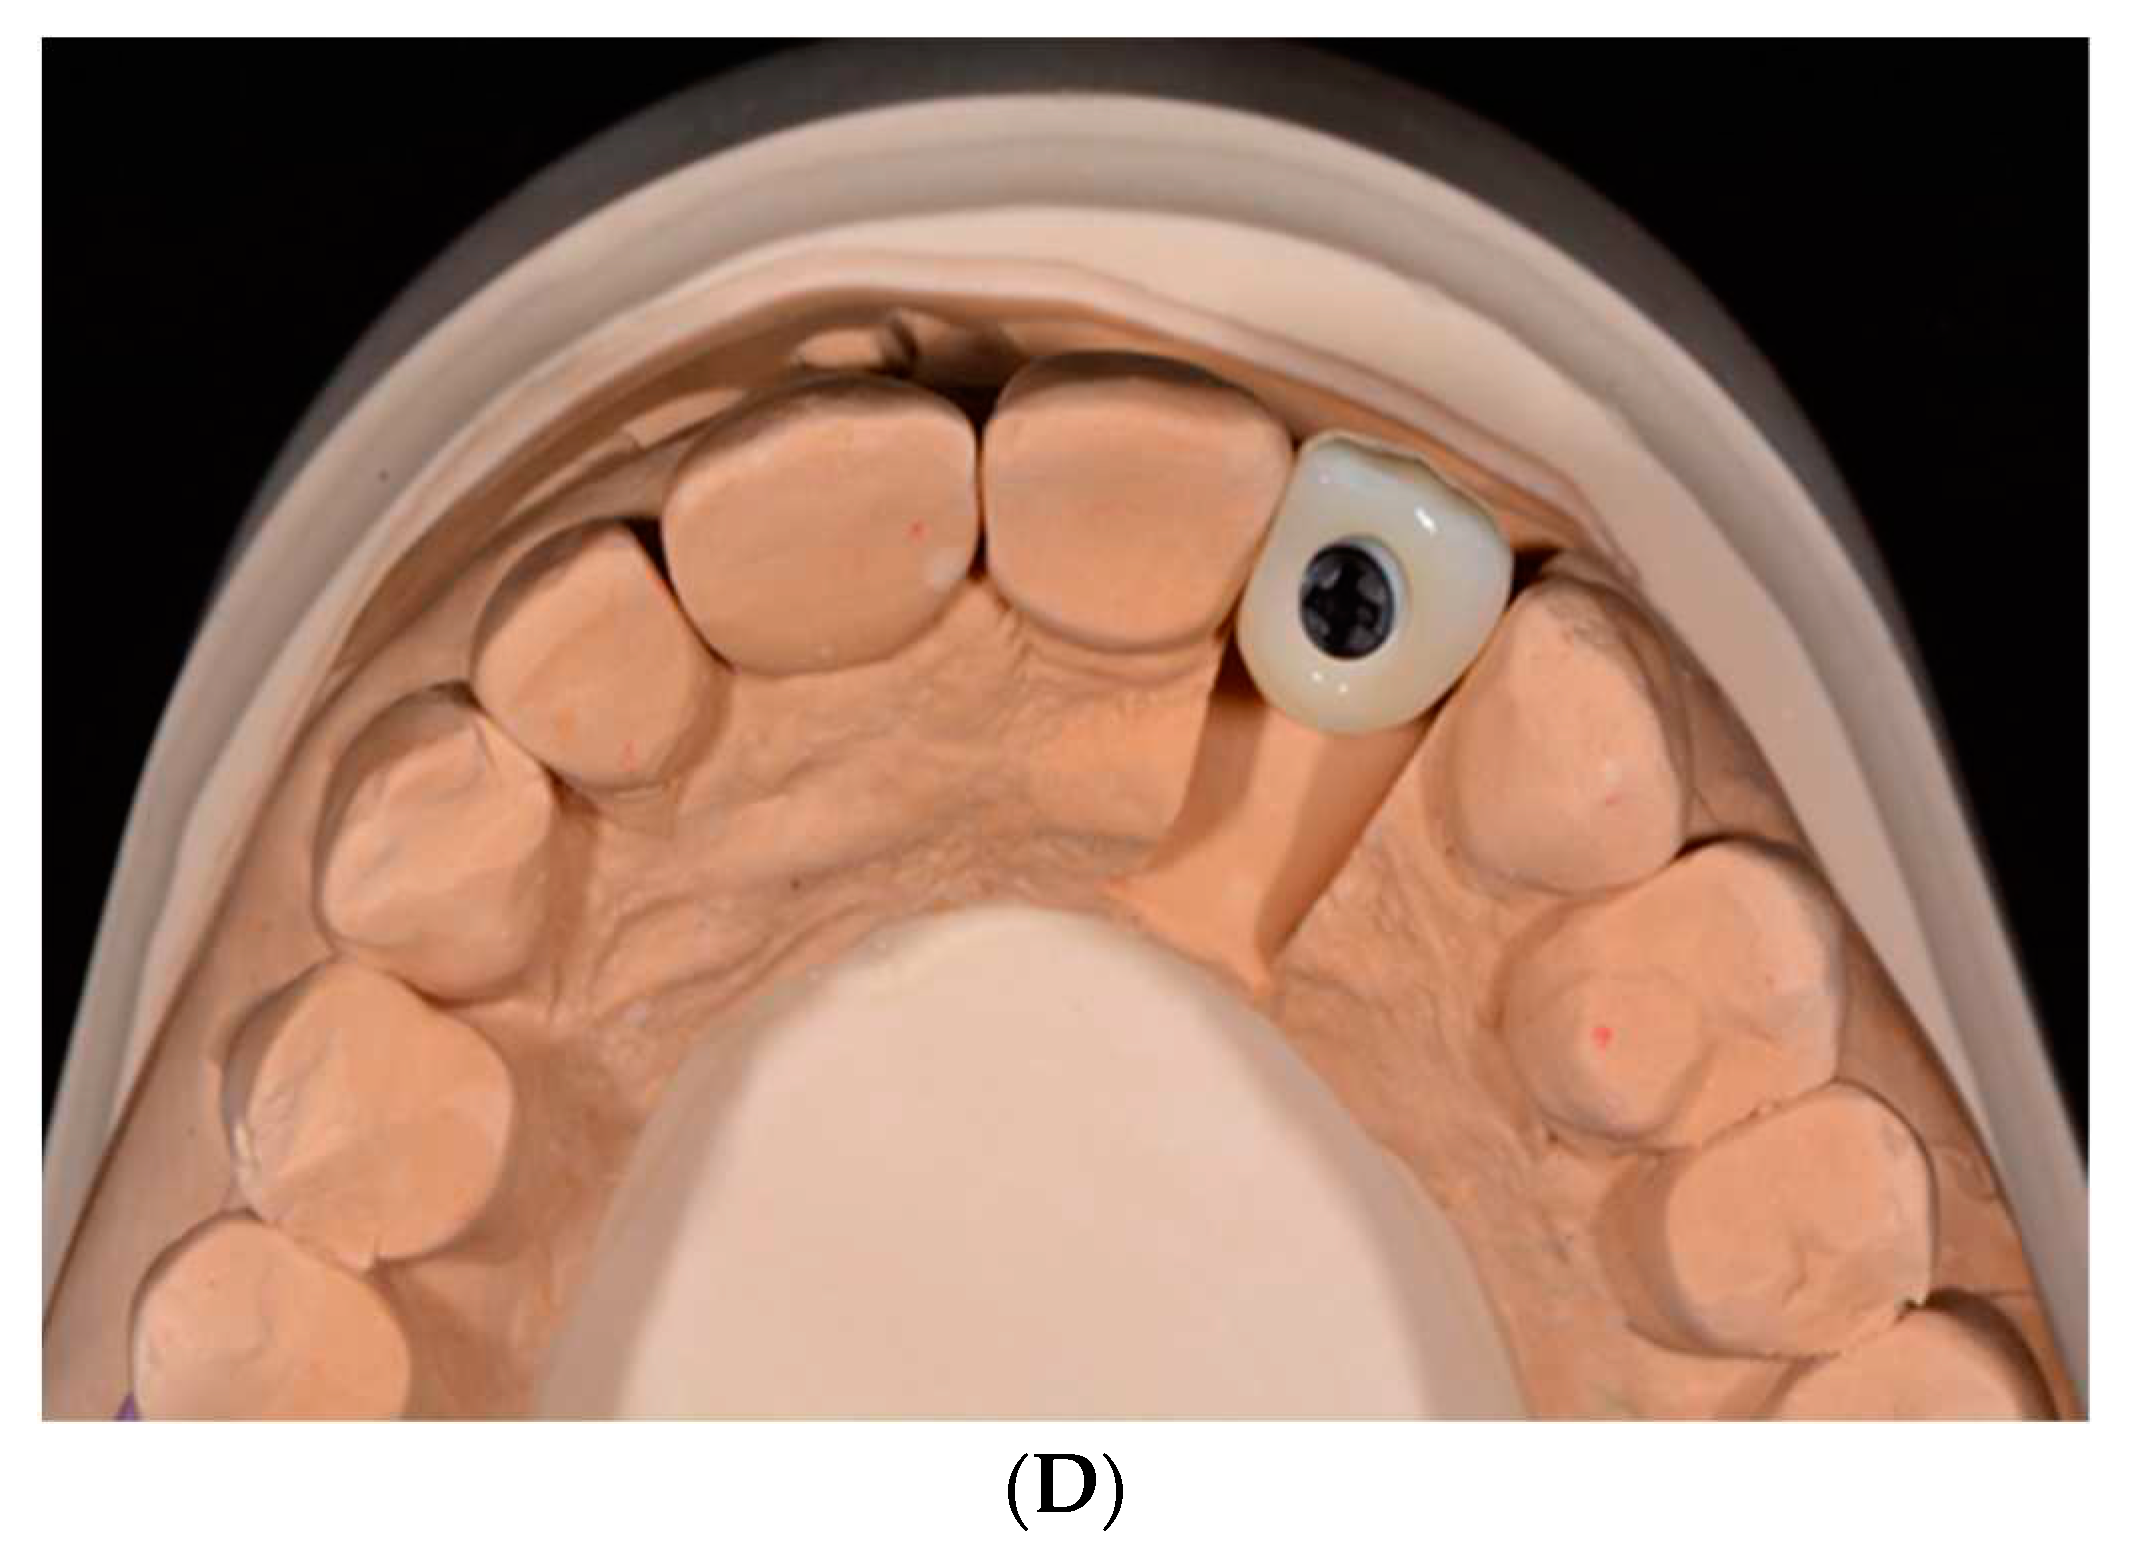

Figure 5. A. Two-piece zirconia implant analog with abutment in place on cast. B. Crown seated on lobular abutment before and after staining and glazing cervical aspect of abutment. C. 2-piece zirconia implant with crown in place and abutment shaded in cervical region. D. Screw-retained design using 2-piece zirconia implant (Courtesy of Alex Rugh).